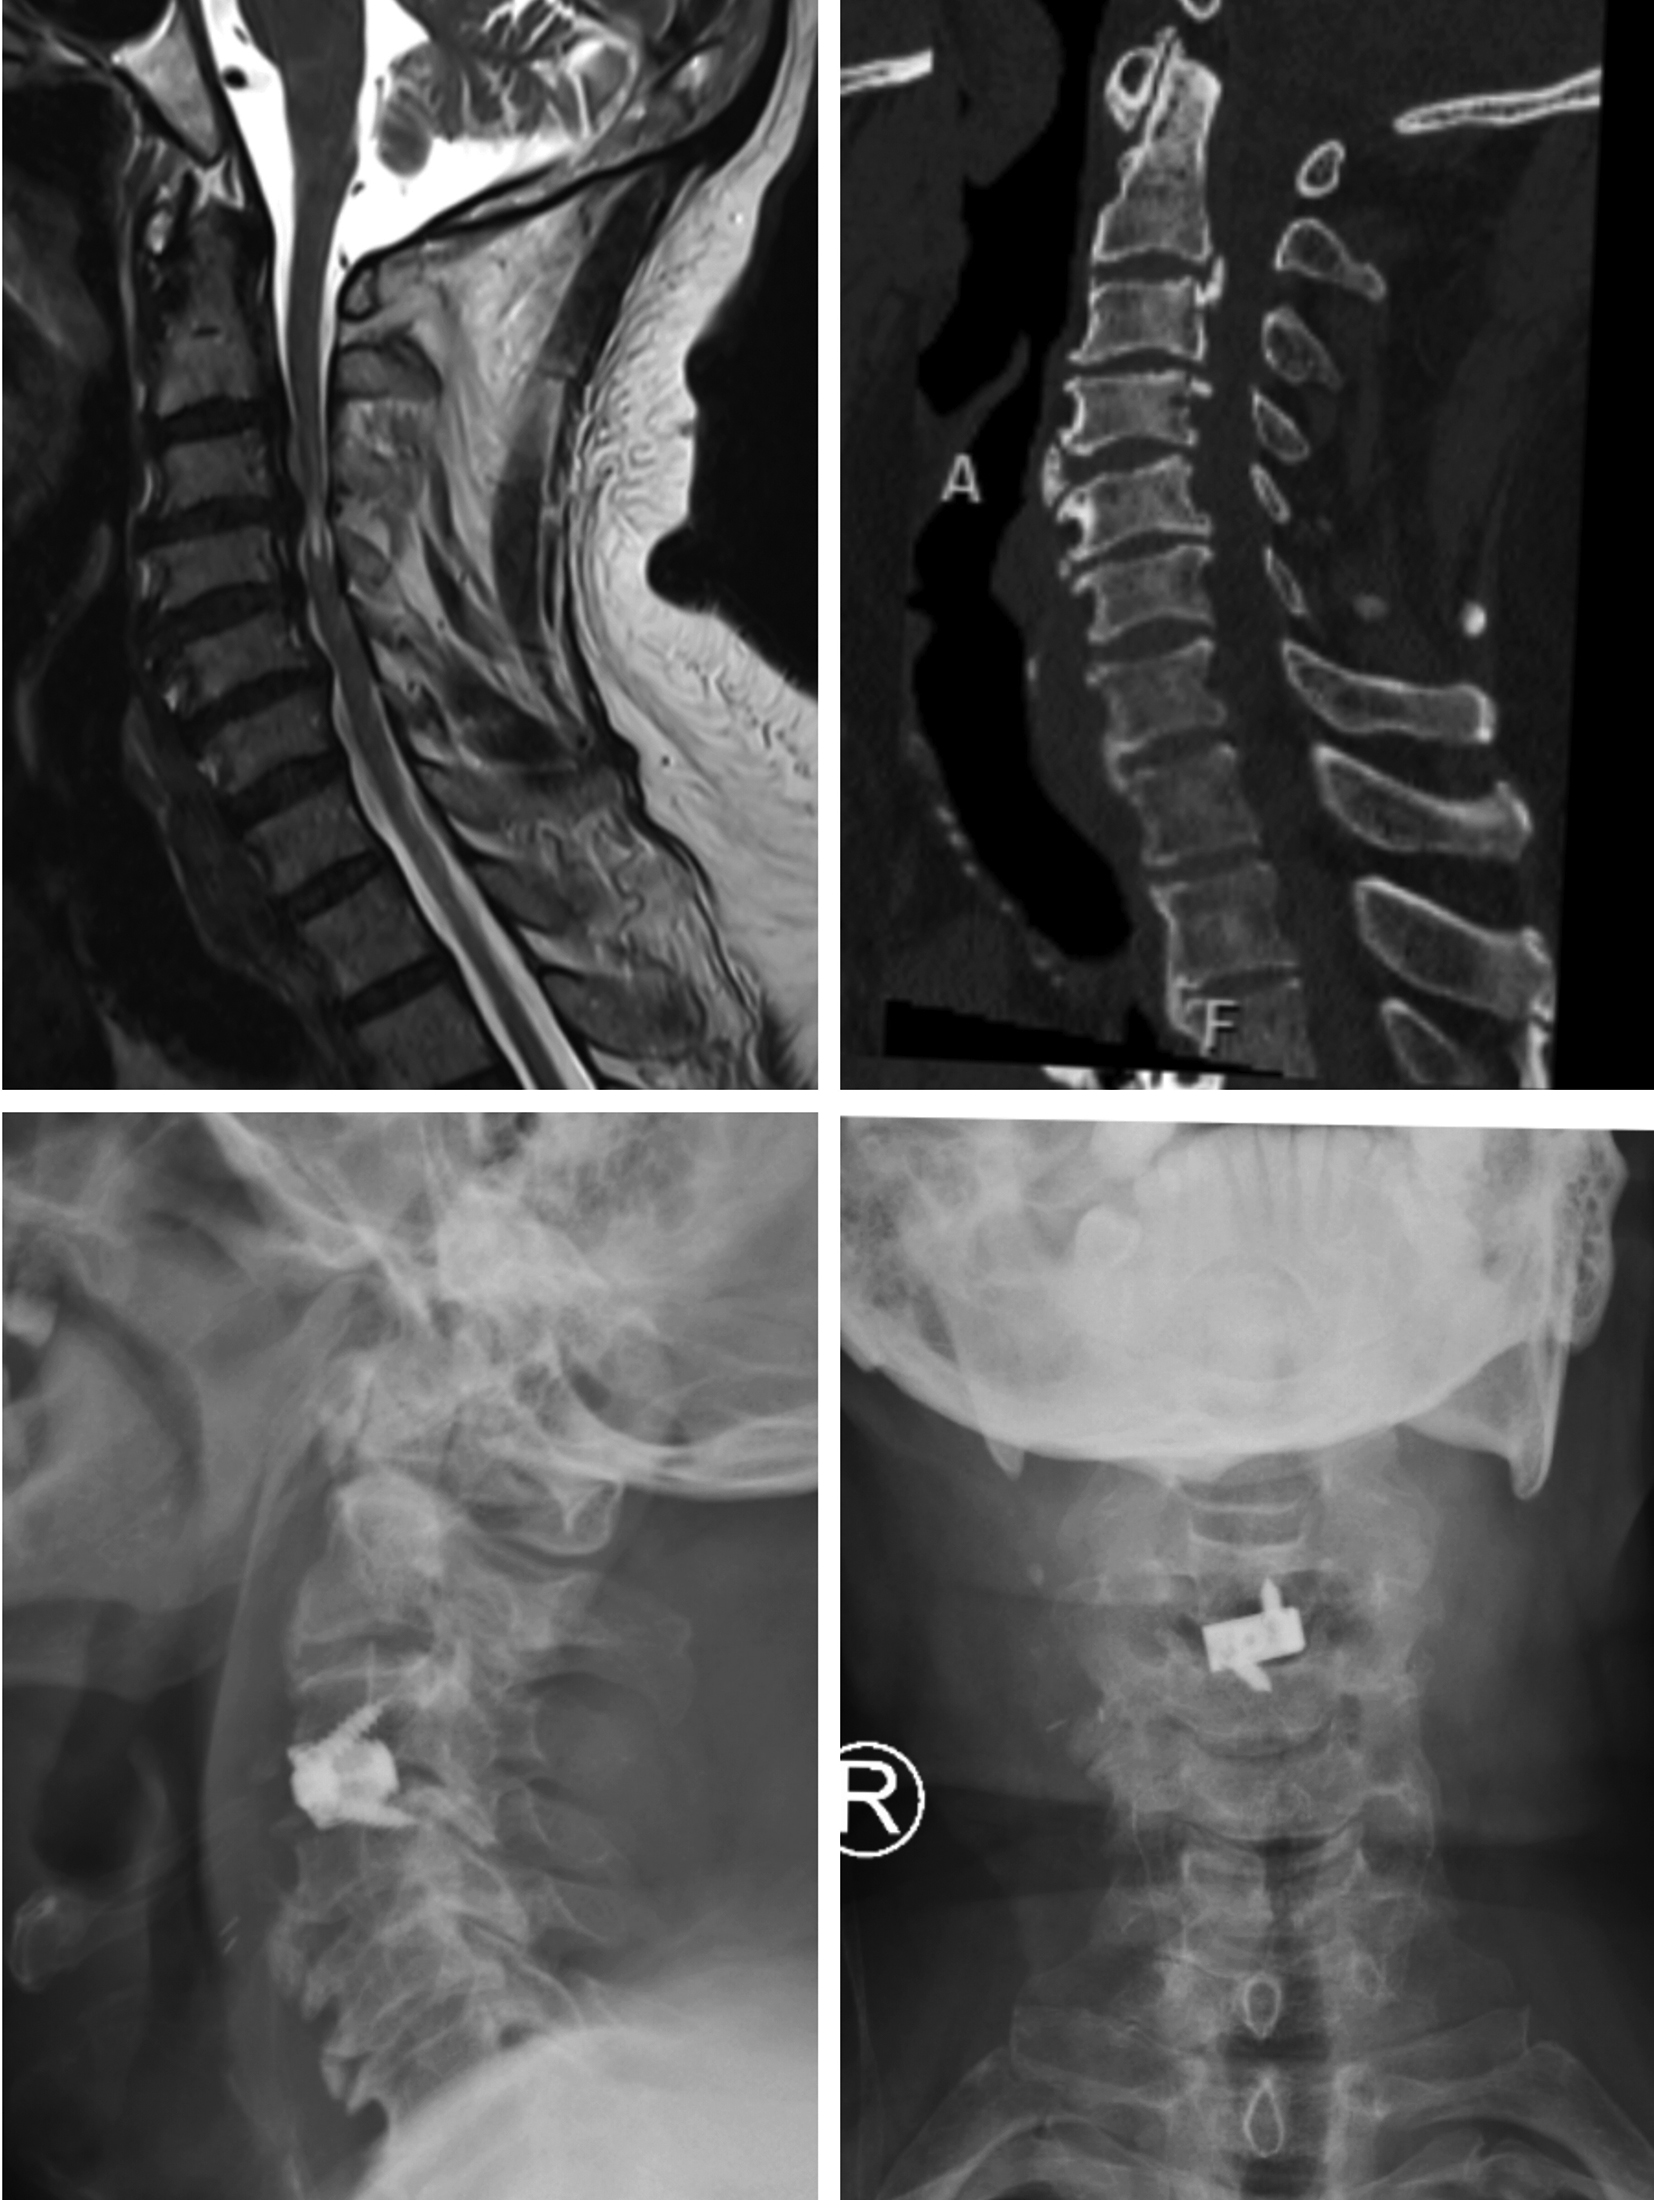

Figures 1-4 show pre-operative and post-operative radiological images in few of our patients.

Figure 1. A - Preoperative magnetic resonance imaging study of the cervical spine, (T2 weighted image, sagittal view) showing narrowing of central canal with cervical compressive myelopathy; B - Preoperative computed tomography imaging study of the cervical spine (sagittal view) showing osteophytes with narrowing of the central canal and straitening of the cervical lordosis; C - Postoperative radiographic imaging study of the cervical spine (sagittal view) showing the cage with screw in situ; D - Postoperative radiographic imaging study of the cervical spine (coronal view) showing the cage with screw in situ